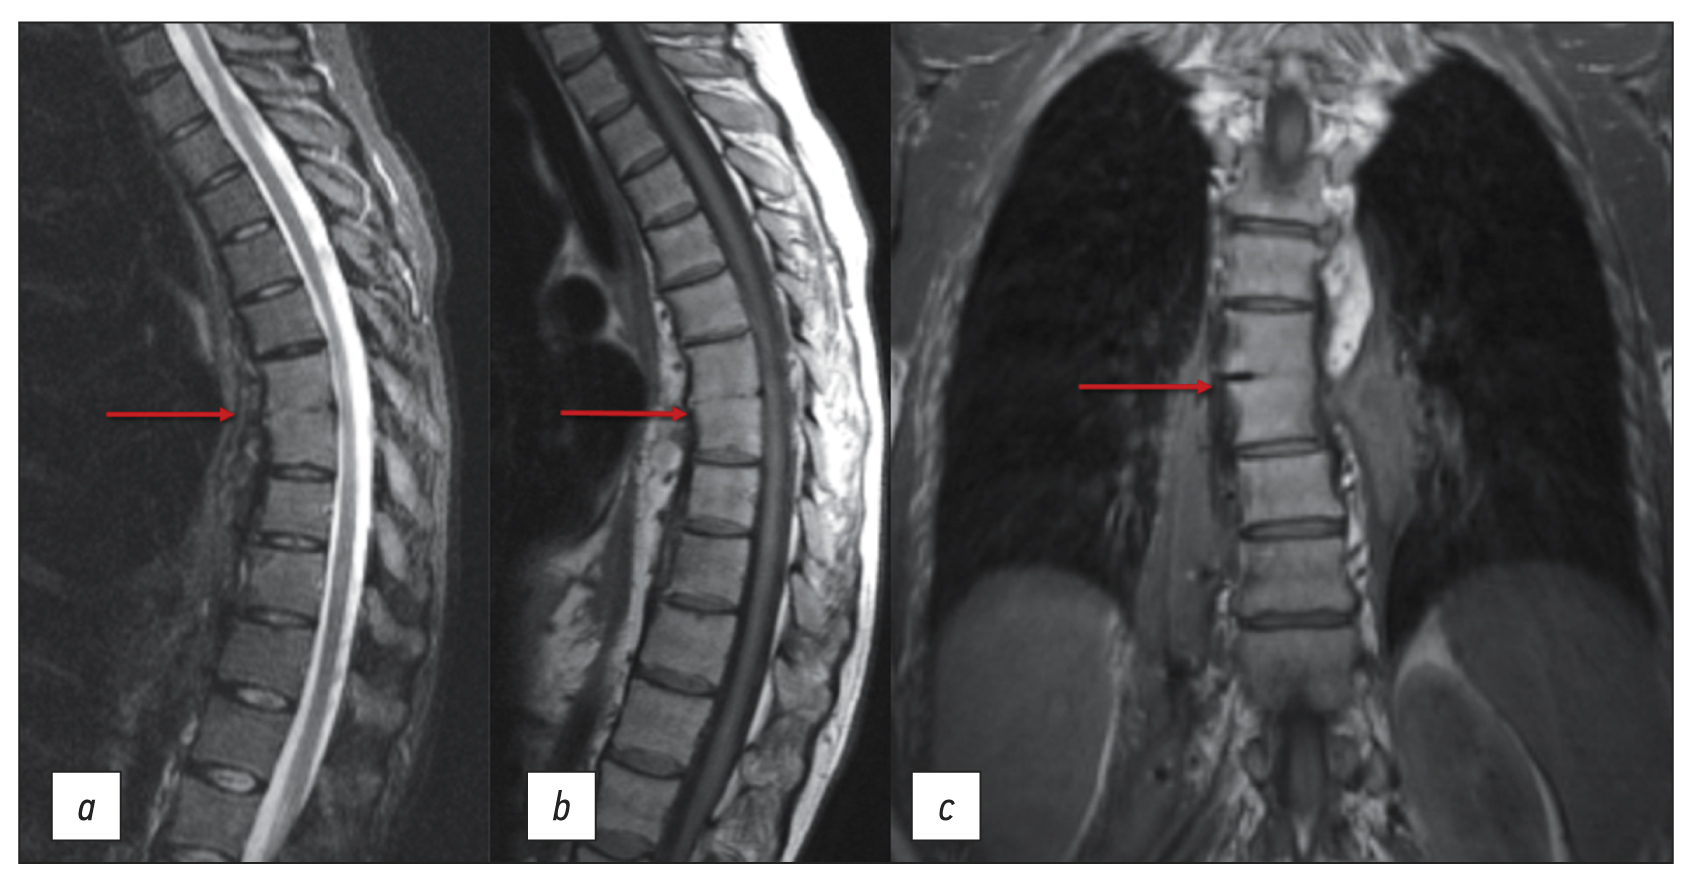

Хронический пищеводный свищ как редкая причина вторичного остеомиелита грудного отдела позвоночника

Аннотация

Инфекционные заболевания позвоночника представляют собой воспалительные деструктивные заболевания органа и его структурных элементов в результате инфицирования гематогенным, лимфогенным или контактным путём, в том числе могут являться осложнением хирургического вмешательства. При постановке диагноза крайне важно оценивать в совокупности анамнез, клиническую картину, а также данные лабораторных исследований и лучевой диагностики.

В работе представлен клинический случай вторично развившегося спондилита позвонков ТhVII–ТhVIII вследствие пищеводного свища. При первичной диагностике спондилит связали со спинальной анестезией, которая проводилась за 6 месяцев до начала заболевания, так как имел место свищевой дефект на коже в поясничной области. По этому поводу трижды проводились оперативные вмешательства в хирургическом стационаре по месту жительства. Данные эндоскопического исследования и жалобы пациентки на связь между приёмами пищи, появлением болей и характером отделяемого из свища не были приняты врачами изначально во внимание. С помощью дополнительного обследования, включающего компьютерную томографию пищевода с пероральным контрастированием и компьютерно-томографическую фистулографию, был установлен основной диагноз «Свищ пищевода», а спондилит грудного отдела позвоночника оказался лишь вторичным осложнением.

Таким образом, окончательный диагноз при болях в спине, обусловленных не только инфицированием, но и являющихся осложнением хирургического вмешательства, должен формулироваться после проведения дифференциальной диагностики с альтернативными заболеваниями позвоночника.